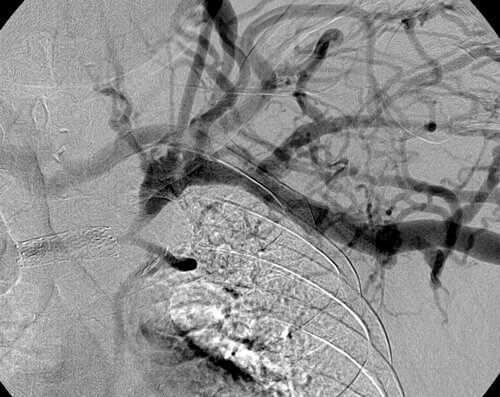

35 year old male patient with CKD requiring hemodialysis via a LUE AV graft. He presents with left upper extremity swelling secondary to a left brachiocephalic vein occlusion.

Comment: This chronic occlusion was treated with stent placement. Unfortunately, the stent occluded within months of placement, necessitating placement of additional stents. This happened again a few months later, requiring angioplasty and covered stent placement.